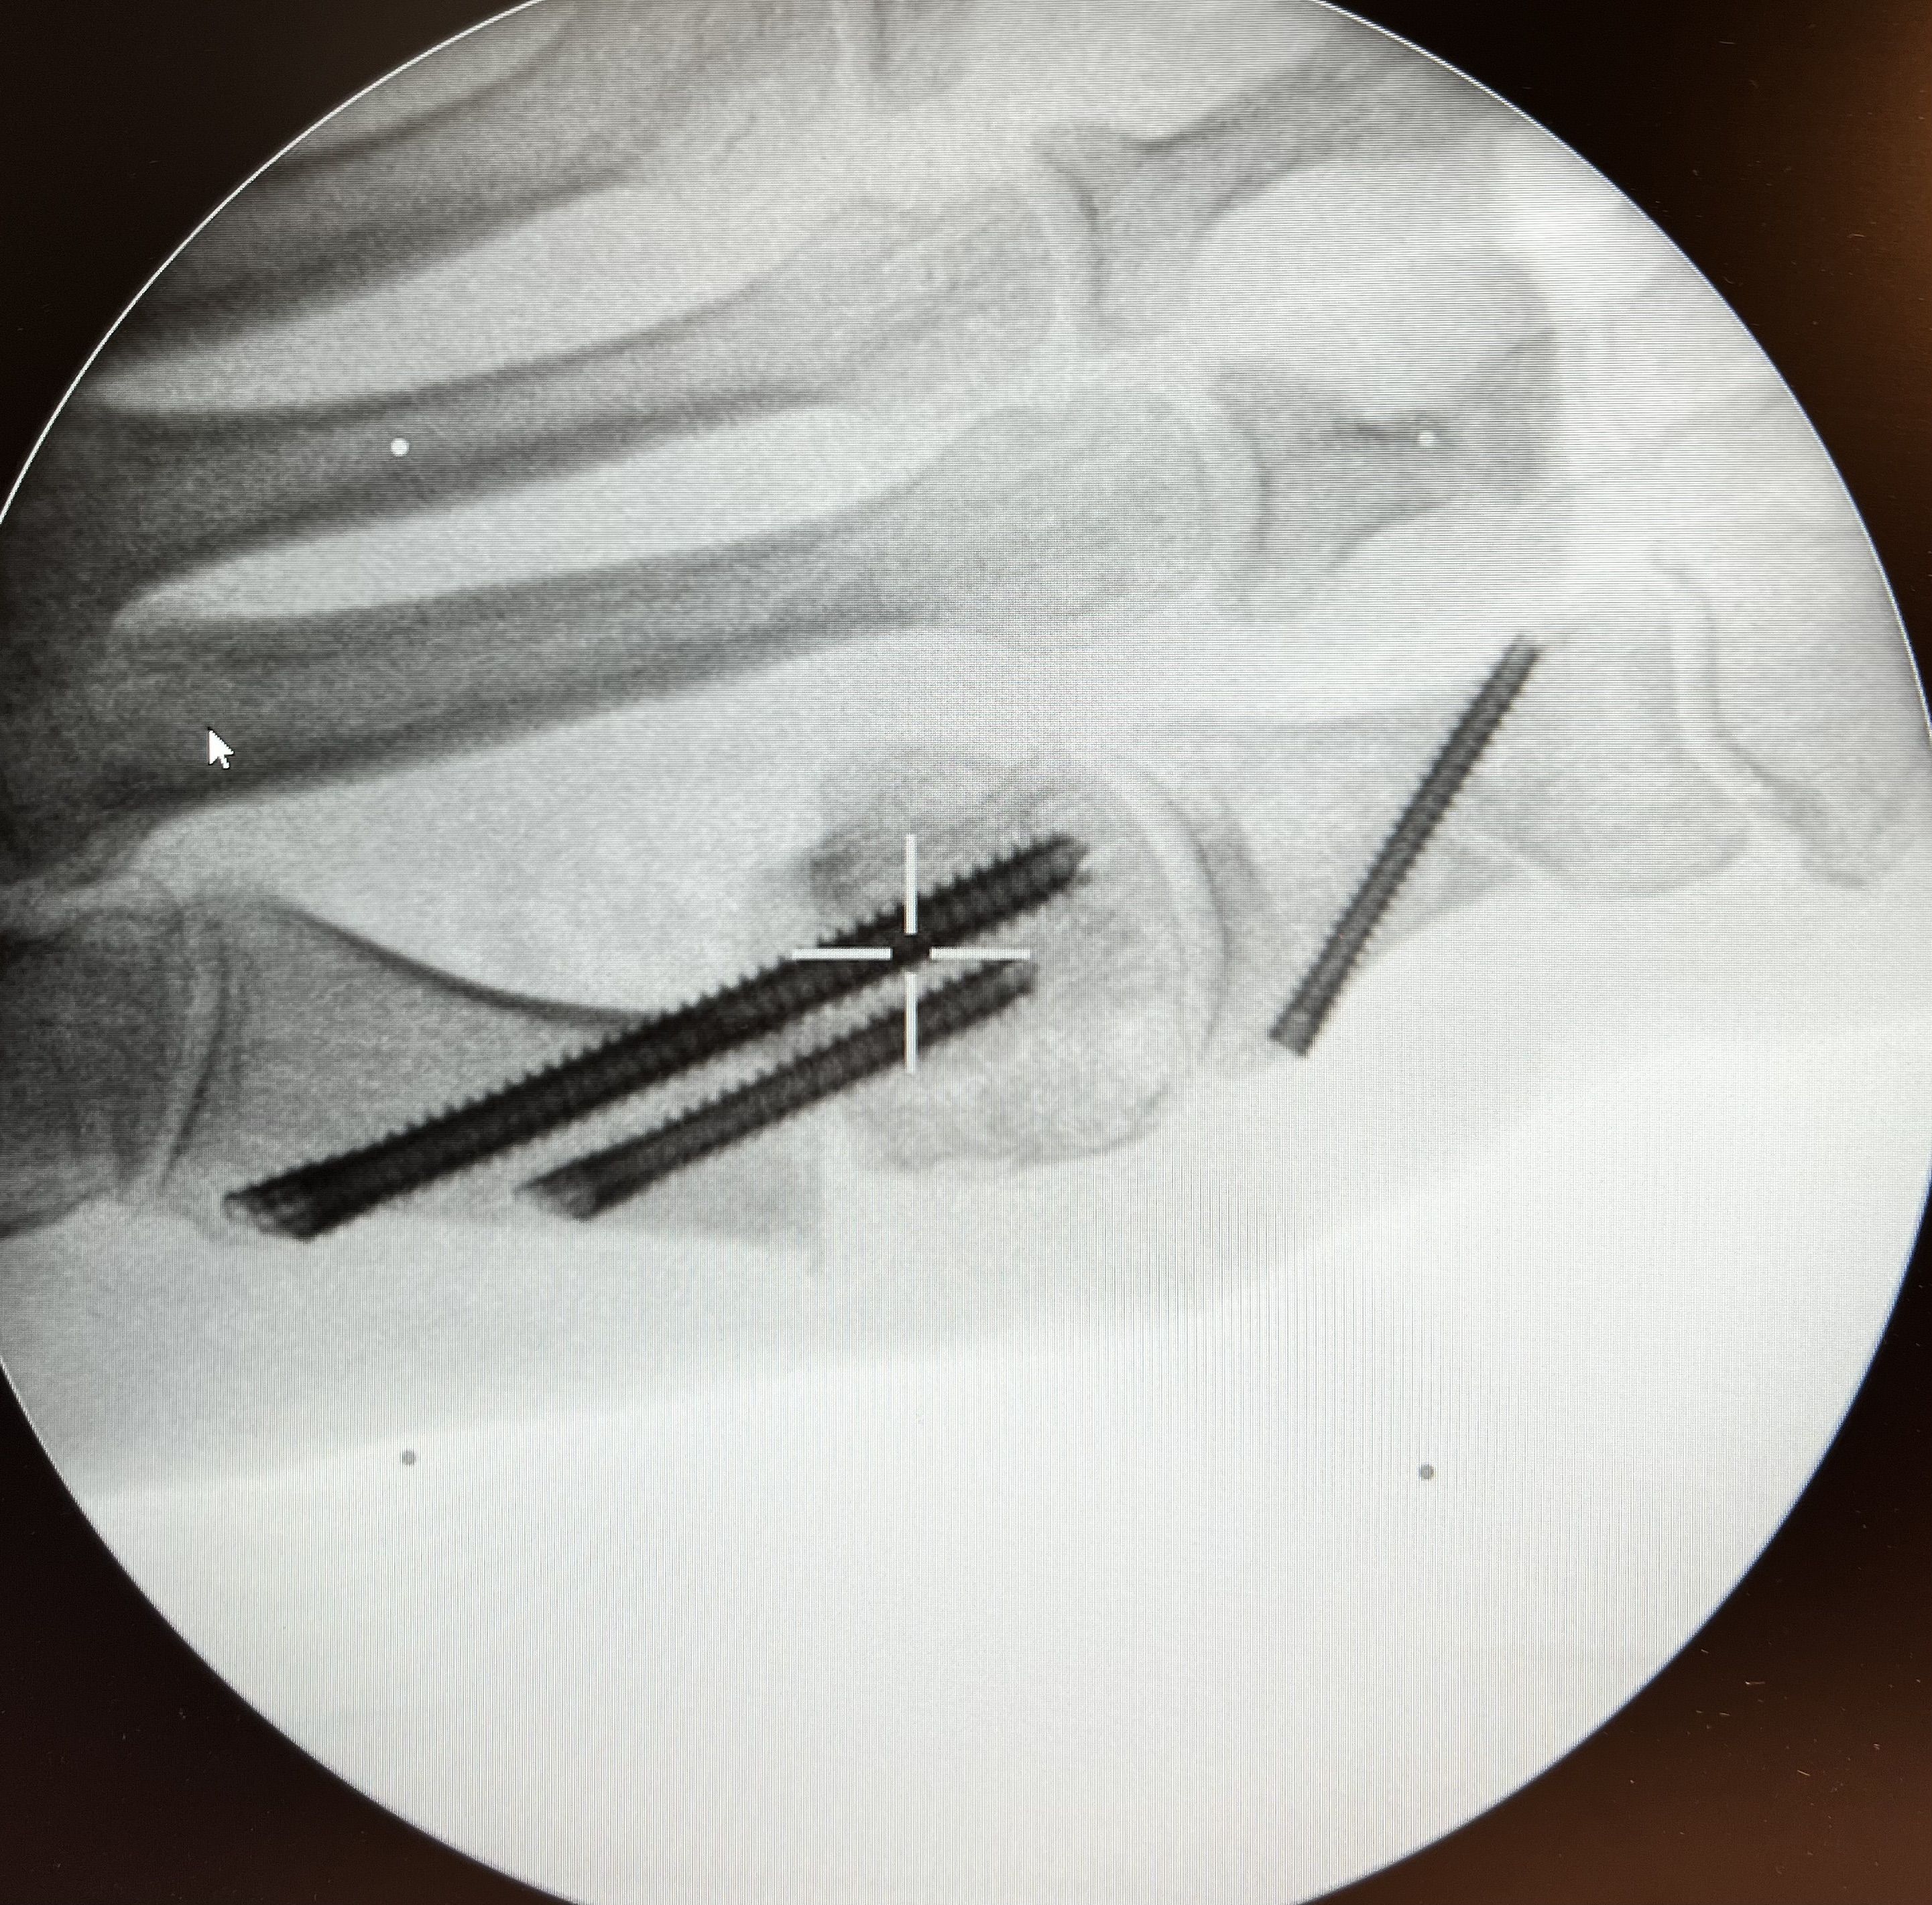

Operative Behandlung

Falls doch eine operative Therapie notwendig werden sollte, können wir diese ambulant in unserem OP-Zentrum anbieten. Hier steht uns ein hochmoderner, vollausgestatteter Operationssaal zur Verfügung.

Gelenkversteifungen (PDF-NACHBEHANDLUNG)

Wann immer möglich werden minimal-invasive Eingriffe durchgeführt. Beispiele hierfür sind eine endoskopische Therapie der Haglund-Exostose, arthroskopische Behandlungen bei Knorpel und Bandverletzungen/Instabilitäten am oberen Sprunggelenk.